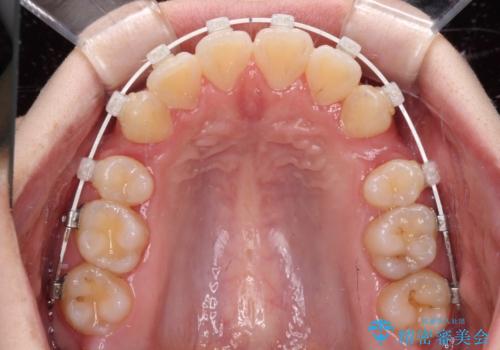

- 矯正装置

- 審美装置

- 2年1ヶ月

- 前歯の出っ歯と口元の閉じにくさを気にして来院された患者様です。

口元を積極的に引っ込めるために、上下左右の小臼歯4本を抜歯することとしました。